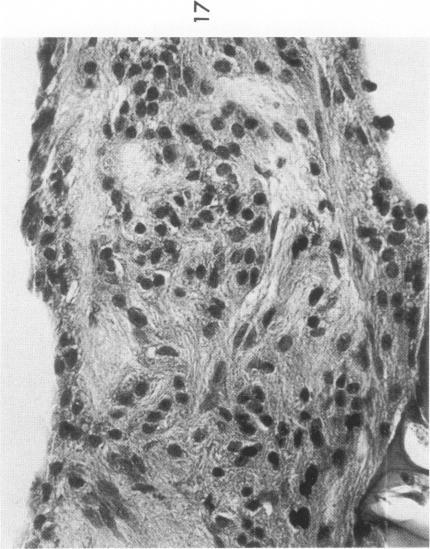

The various stages of divergent neuroepithelial differentiation were studied in the solid transplants of a transplantable mouse testicular teratoma (OTT-6050) maintained in both ascitic and solid forms. They included: a) areas of undifferentiated medullary epithelium corresponding to the rare human medulloepithelioma; b) areas of neuroblastic differentiation corresponding to neuroblastoma, with more mature neuronal differentiation corresponding to ganglioneuroma or, when mixed with glial elements, to ganglioglioma; and c) more mature neuroglial areas resembling astrocytoma, oligodendroglioma or ependymoma, as well as more primitive areas corresponding to ependymoblastoma. In tissue culture using collagen-coated coverslips, astrocytic differentiation was found in the outgrowth zone after 15 days, confirmed by immunofluorescence with antibodies to an astroglia-specific protein. In organ culture systems, glial components, including ependymal structures, were preserved in tumor explants, and astrocytic differentiation, as expressed by glial fiber formation, was increased after 4 to 6 weeks in vitro. No neuronal differentiation was demonstrable, however. The neuroepithelial component of this experimental teratoma may provide a model for the study of neoplastic neuroepithelial differentiation.

在以腹水和实体形式维持的可移植小鼠睾丸畸胎瘤(OTT - 6050)的实体移植中,研究了神经上皮分化的各个阶段。这些阶段包括:a)与罕见的人类髓上皮瘤相对应的未分化髓上皮区域;b)与神经母细胞瘤相对应的成神经细胞分化区域,与神经节神经瘤相对应的更成熟的神经元分化区域,或者当与神经胶质成分混合时,与神经节胶质瘤相对应的区域;c)更成熟的类似星形细胞瘤、少突胶质细胞瘤或室管膜瘤的神经胶质区域,以及与室管膜母细胞瘤相对应的更原始区域。在使用胶原包被盖玻片的组织培养中,15天后在生长区发现了星形细胞分化,用抗星形胶质细胞特异性蛋白的抗体进行免疫荧光证实。在器官培养系统中,肿瘤外植体中保留了包括室管膜结构在内的神经胶质成分,体外培养4至6周后,以胶质纤维形成为特征的星形细胞分化增加。然而,未发现神经元分化。这种实验性畸胎瘤的神经上皮成分可能为肿瘤性神经上皮分化的研究提供一个模型。